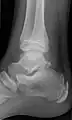

Ankle

Accessory bones of the ankle.[13]

Accessory bones at the ankle mainly include:

• Os subtibiale, with a prevalence of approximately 1%.[14] It is a secondary ossification center of the distal tibia that appears during the first year of life, and which in most people fuses with the shaft at approximately 15 years in females and approximately 17 years in males.[14]

• Os subfibulare, with a prevalence of approximately 0.2%.[15]

Os trigonum (further described below) may also be seen on an ankle X-ray.